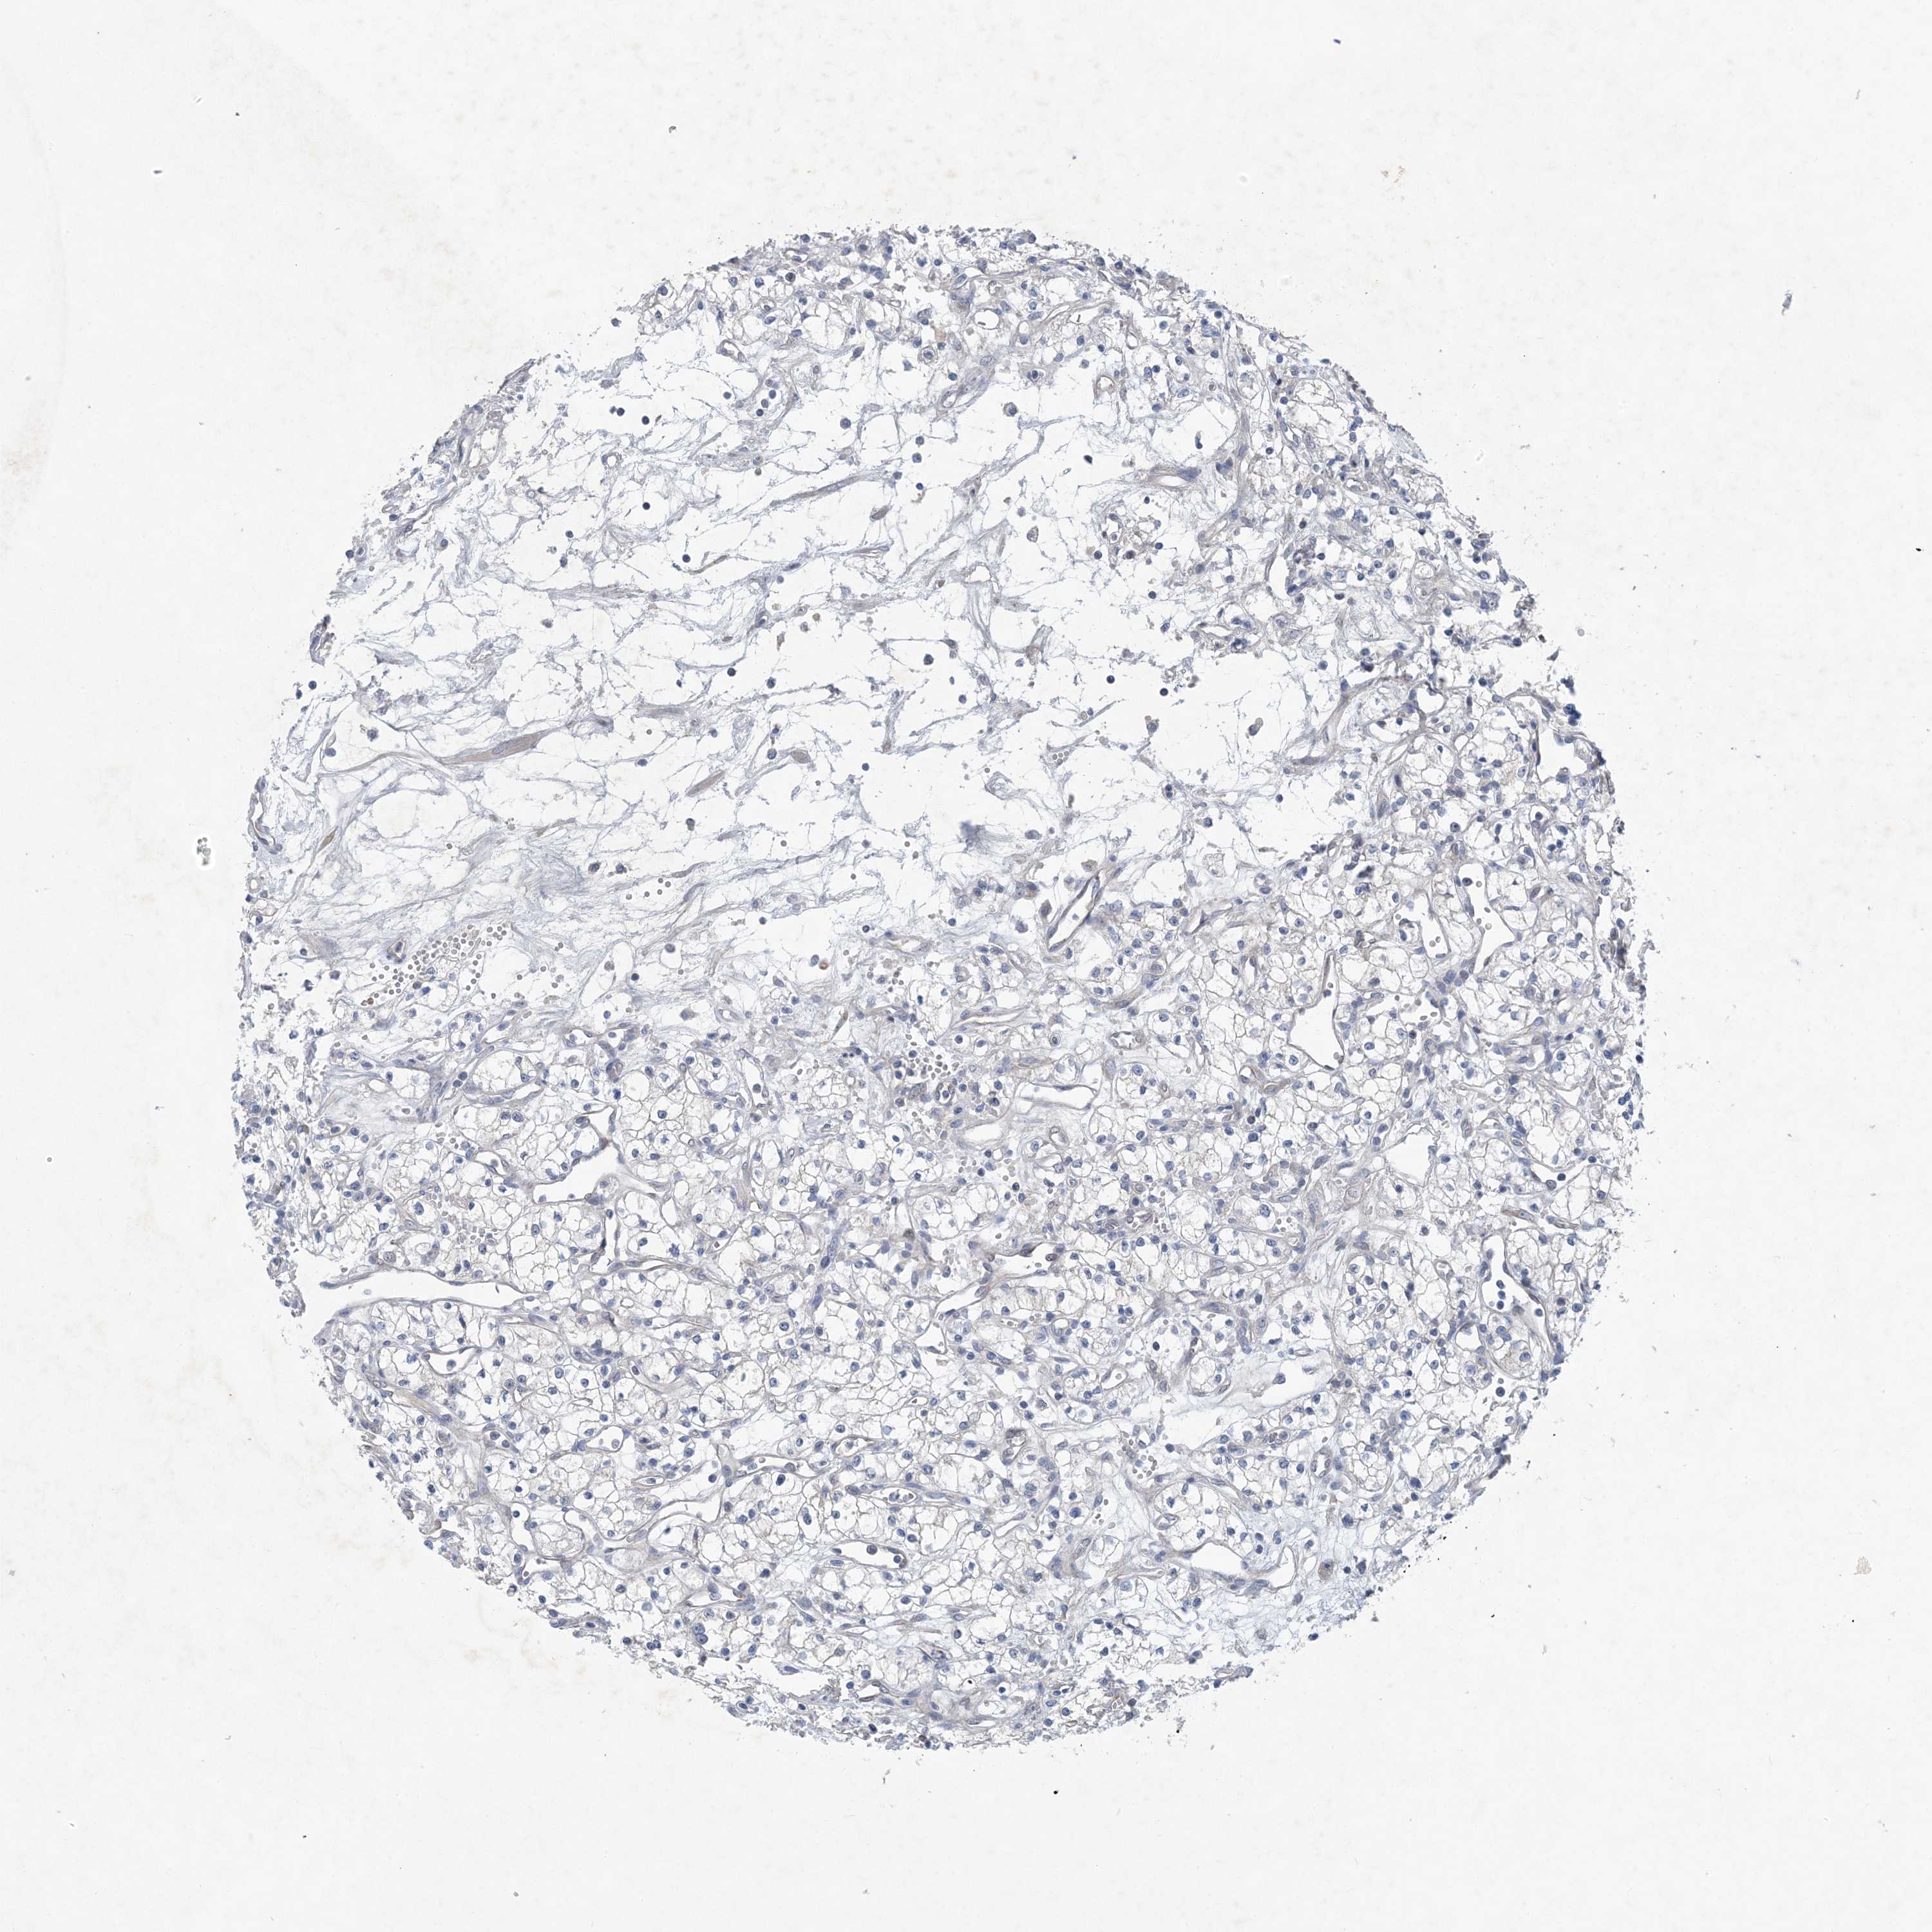

KIDNEY RENAL PAPILLARY CELL CARCINOMA (TCGA) - Interactive survival scatter ploti

The Survival Scatter plot shows the clinical status (i.e. dead or alive) for all individuals in the patient cohort, based on the same data that underlies the corresponding Kaplan-Meier plots. Patients that are alive at last time for follow-up are shown in blue and patients who have died during the study are shown in red.

The x-axis shows the expression levels (FPKM) of the investigated gene in the tumor tissue at the time of diagnosis. The y-axis shows the follow-up time after diagnosis (years). Both axes are complimented with kernel density curves demonstrating the data density over the axes. The top density plot shows the expression levels (FPKM) distribution among dead (red) and alive patients (blue). The right density plot shows the data density of the survived years of dead patients with high and low expression levels respectively, stratified using the cutoff indicated by the vertical dashed line through the Survival Scatter plot. This cutoff is automatically defined based on the FPKM cutoff that minimizes the p-score. The cutoff can be changed by dragging the vertical line or by entering a cutoff value in the square labeled "Current cut-off".

Under the Survival Scatter plot the p-score landscape (black curve; left axis) is shown together with dead median separation (red curve; right axis). Dead median separation is the difference in median mRNA expression between patients who have died with high and low expression, respectively. It is calculated as follows: median FPKM expression of dead patients with high expression - median FPKM expression of dead patients with low expression. This is intended to aid the user in visually exploring custom cutoffs and the associated p-scores and dead median separation.

Individual patient data is displayed and can be filtered by clicking on one or more of the category buttons on the top of the page. Categories describing expression level and patient information include: high, low, alive, dead, female, male and tumor stages. The scale of the x-axis can be toggled between linear and log-scale by clicking on the "x log" button. Mouse-over function shows TCGA ID, patient information and mRNA expression (FPKM) for each patient.

& Survival analysisi

Kaplan-Meier plots summarize results from analysis of correlation between mRNA expression level and patient survival. Patients were divided based on level of expression into one of the two groups "low" (under cut off) or "high" (over cut off). X-axis shows time for survival (years) and y-axis shows the probability of survival, where 1.0 corresponds to 100 percent.

HIKESHI is not prognostic in Kidney Renal Papillary Cell Carcinoma (TCGA)